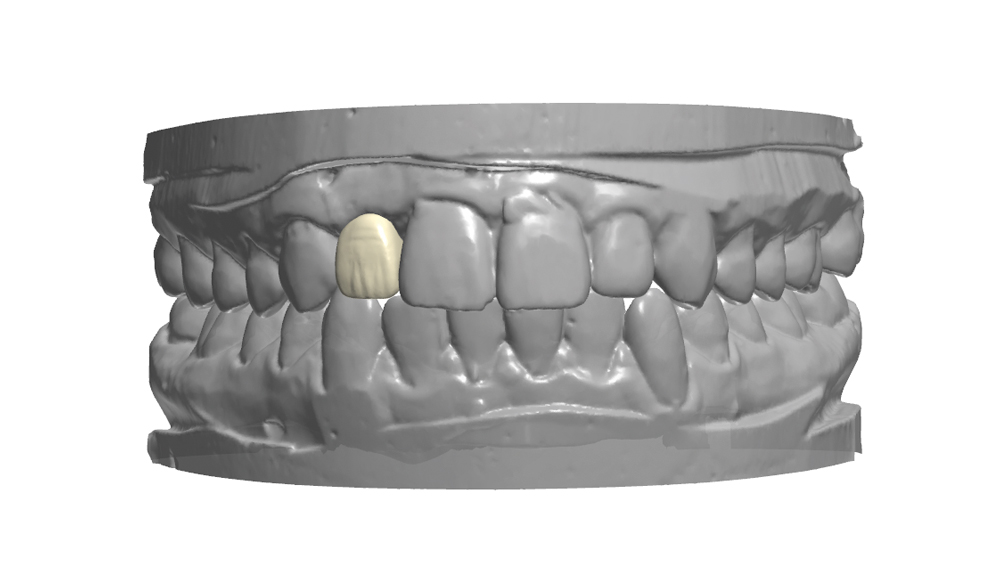

The following case illustrates the efficient, straightforward clinical workflow for placing Hahn Tapered Implants via guided surgery. A digital treatment plan is developed in which a 3.5 mm implant is positioned to support the ideal prosthetic outcome. An immediate provisional crown is designed in concert with the surgical guide and delivered at the time of surgery, helping to produce a predictable, highly esthetic restoration for a demanding case in the smile zone.